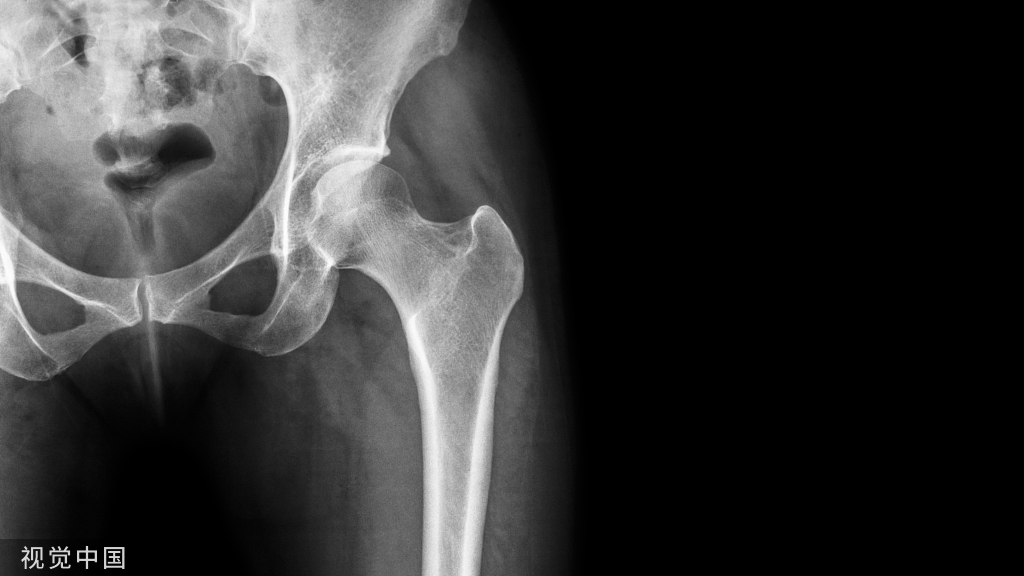

新 月 征

髋关节 X 线平片示右侧股骨头关节面下新月形透亮影,提示新月征

判读要点:

1、新月征是 III 期股骨头坏死的直接征象;

2、新月征对诊断股骨头坏死具有特异性,提示股骨头早期塌陷;3、在 X 线骨盆或髋关节正位片显示。